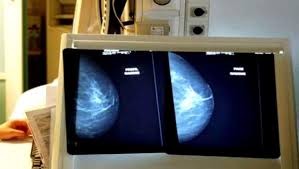

Lutte contre le cancer : Les polycliniques seront progressivement équipées de mammographies

Les polycliniques seront progressivement équipées de mammographes afin de renforcer le dépistage du cancer du sein et de desserrer la pression sur les hôpitaux, a indiqué hier à Alger le ministre de la Santé, de la Population et de la Réforme hospitalière, Abdelmalek Boudiaf.

«On équipera progressivement les polycliniques pour que les mammographies puissent devenir un geste automatique», a déclaré le ministre lors de la journée scientifique sur le dépistage du cancer du sein en milieu professionnel organisée par l’association El Amel.

M. Boudiaf compte sur ces structures afin de réaliser les objectifs «du plan de dépistage précoce du cancer du sein» sans omettre le dépistage en milieu professionnel.